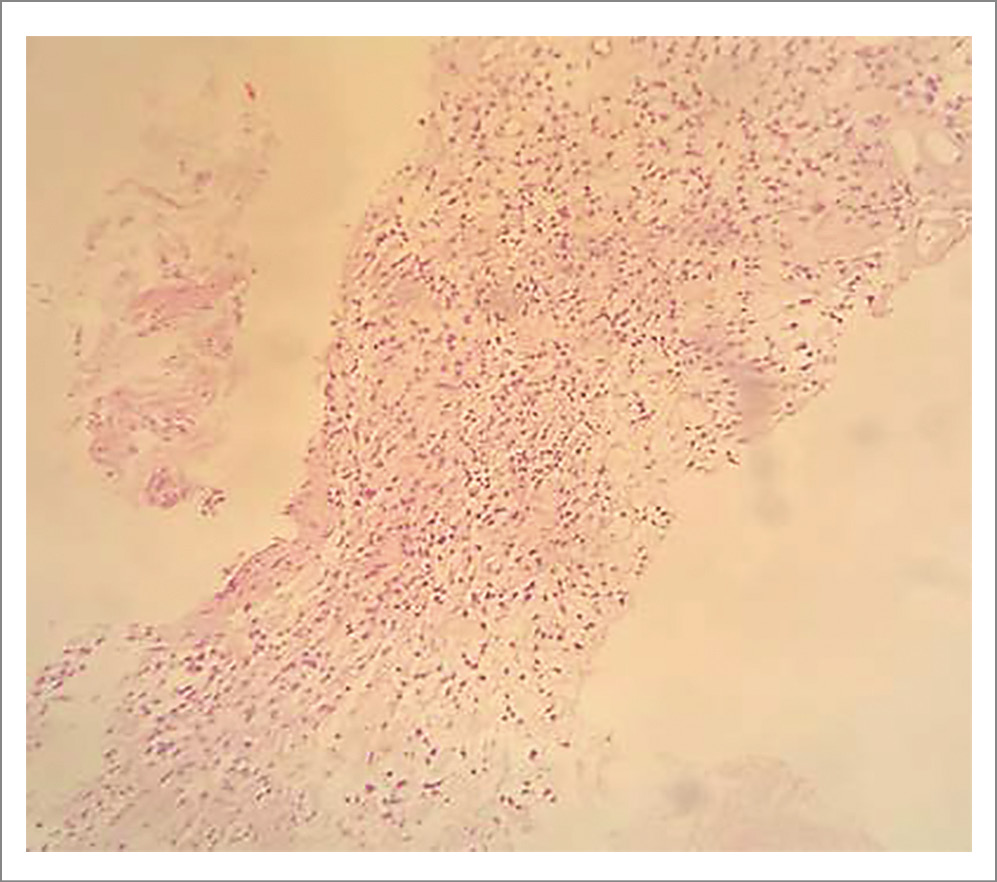

При патогистологическом исследовании биоптата из семенного пузырька обнаружена опухоль солидного строения с обилием гиалинизированных и щелевидных сосудов. Короткие веретеновидные опухолевые клетки расположены диффузно с умеренным полиморфизмом и вакуолизированными ядрами. Митозы не обнаружены (рис. 3).

Рис. 3. Пациент М. Гистологическая картина биоптата из семенного пузырька представлена диффузно расположенными веретеновидными опухолевыми клетками с умеренным полиморфизмом (окраска гематоксилином и эозином, увеличение ×20).